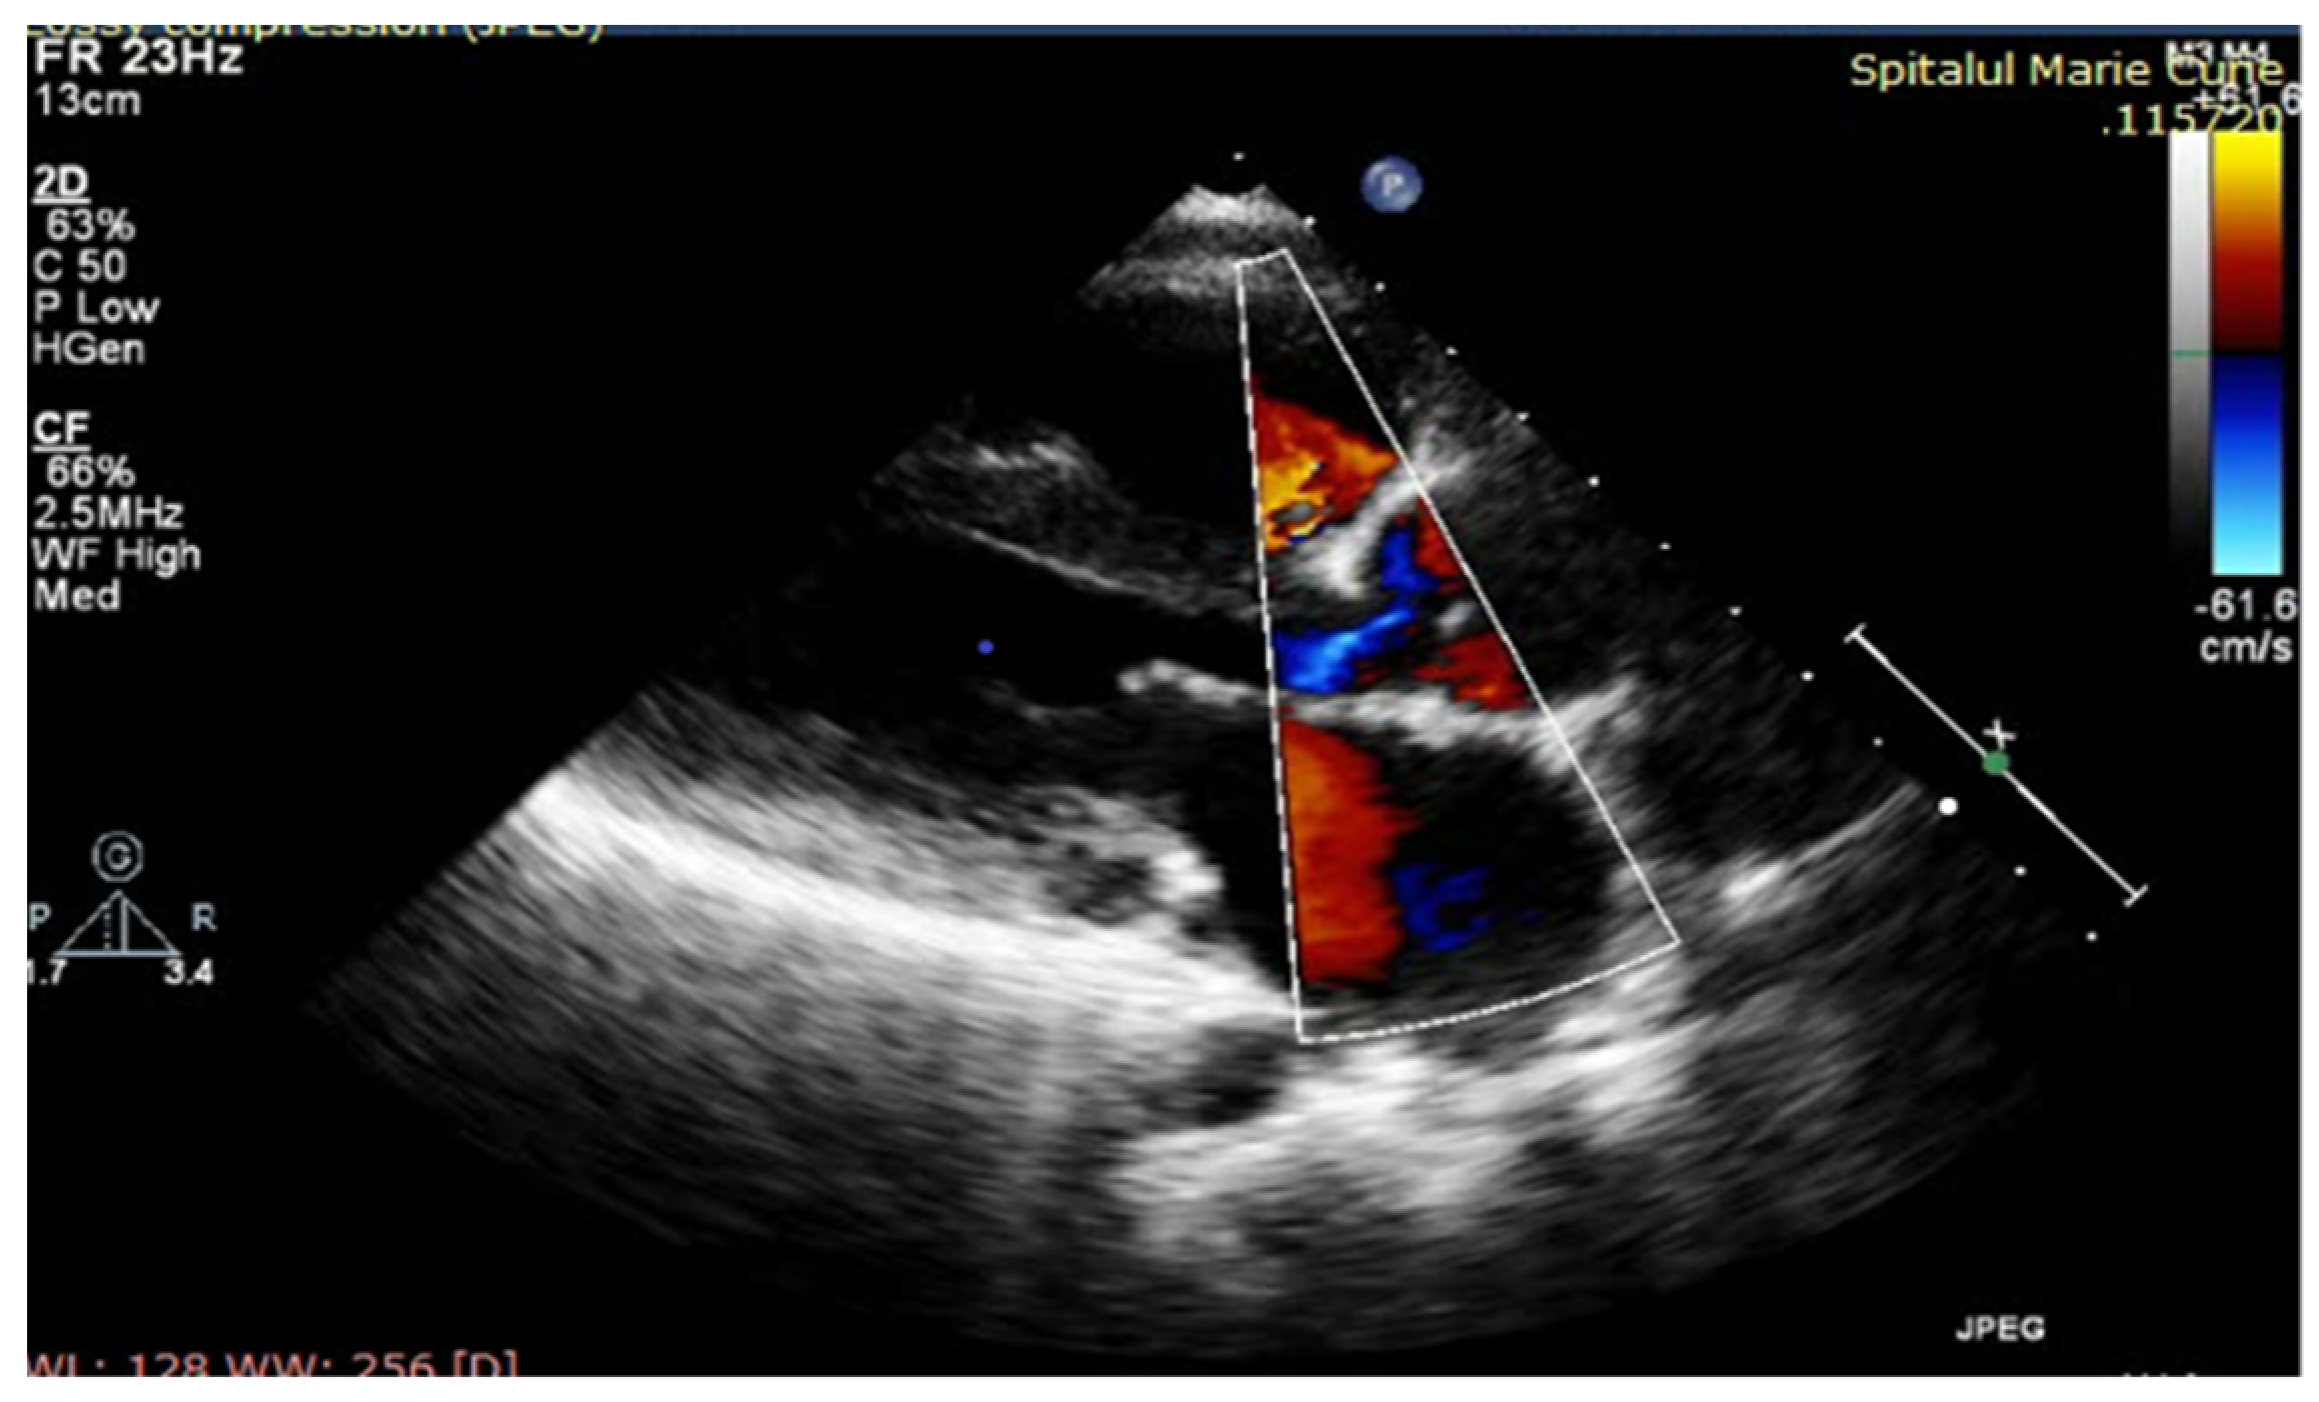

After completing antibiotic therapy (6 weeks), the patient was in a relatively good clinical condition, with reasonable control of hypertension (secondary to aortic coarctation), dyspnea on moderate exertion, an IV/VI-grade systolic murmur in the aortic area, marked diastolic murmur, mild anemia and regular inflammatory tests. Transthoracic echocardiography (Figure 2) revealed moderate aortic valve stenosis, severe aortic regurgitation, severe aortic coarctation, progressive dilatation and decreased LV systolic function (LVEF = 35%). Unexpectedly, muscle enzymes increased over the next two weeks to a high serum level, especially CK, whose serum level range was 3800–8500 Ui/L. During the first phase of endocarditis evolution, high cardiac, liver and muscle enzyme levels were interpreted in the context of LV systolic dysfunction (secondary to severe acute aortic insufficiency and possible coronary flow steal) associated with a potential adverse reaction of cytolysis-causing drugs. However, the increasing trend of these blood tests, along with some motor features, such as Gowers’ sign and staggering gait, required a neurological examination, raising the suspicion of hereditary muscular dystrophy. Multiplex-ligation-dependent probe amplification (MLPA) was used as the diagnostic test (from a peripheral blood sample) and confirmed the presence of dystrophin mutation and Duchenne disease. Based on the high peri-operative risk of cardiac intervention, the child was referred to a more experienced cardiac surgery unit for surgery. Within four weeks after IE recovery, the boy underwent a complex surgery consisting of a Ross operation (aortic autograft, pulmonary homograft) and coarctectomy. Immediate postoperative evolution was severe, with cardiac arrest being resuscitated 36 h after surgery, requiring five days of extracorporeal membrane oxygenation (ECMO). The evolution was slow and favorable, necessitating challenging discontinuation of mechanical respiratory support and persistence of clinical heart failure and 21 days of hospitalization in the intensive care unit. Initial postoperative echocardiography revealed good neoaortic valve function, good pulmonary homograft functionality, residual large aortic coarctation and severe LV and RV systolic dysfunction (LVEF = 20%). The patient was discharged five weeks after surgery in good clinical condition with improved exercise tolerance.

Echocardiography performed at discharge evidenced slowly improving kinetics in both ventricles, with LVEF = 35% and LVEF = 45% at discharge (Figure 2).

Figure 2. TTE: A5CH (modified): severe aortic regurgitation.